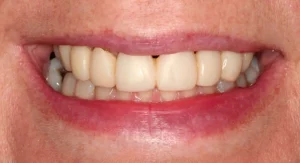

When this lady was younger, she had four teeth removed and then braces placed. However, the patient didn’t like her end smile; she felt it looked too narrow, so she sought more treatment.

At the beginning of treatment, the top gaps were too narrow to place the correct size of the premolar tooth. So braces were put on, and the gaps were opened up. When we achieved enough space, we could place the implants on either side of the top jaw. Porcelain crowns were placed on the implants. A while later, we added composite bonding on other teeth to further improve the patient’s bite, bringing additional comfort to her facial muscles and jaws.